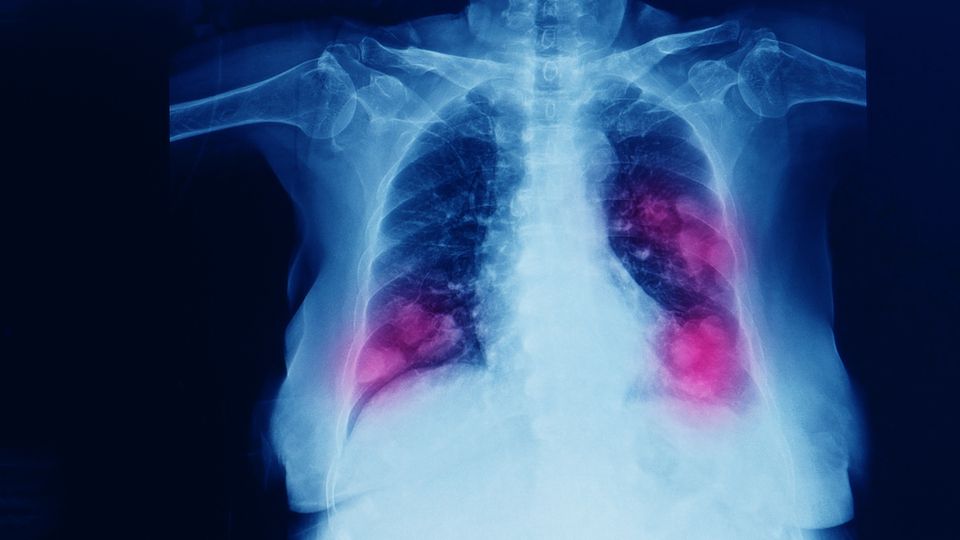

Arjantin'de dokuz kişide gizemli zatürre (pnömoni) tespit edilmesinin ardından, üç kişi hayatını kaybetti. Tucumán eyaletindeki Sağlığı Bakanlığından yapılan açıklamada, Arjantin'de iki taraflı zatürree (her iki akciğeri de etkileyen zatürree) ile hastaneye kaldırıldıktan sonra üç kişinin öldüğünü ve doktorların hastalığa neyin neden olduğunu bulmaya çalıştığını duyurdu.

Gizemli zatürreye yakalanan hastalarda ateş, karın ağrısı, nefes darlığı ve kas ağrıları şikayetlerin olduğu belirtildi.